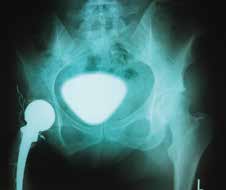

Die Besonderheit der hier vorgestellten Versorgung besteht zum einen darin, dass bisher kein Wechsel der Hüft-TEP stattgefunden hat und die Patientin somit seit 39 Jahren mit derselben TEP versorgt ist. Zum anderen haben sich die Stumpfverhältnisse in den letzten ca. zehn Jahren hinsichtlich Weichteildeckung, Belastbarkeit und Schmerzempfinden verschlechtert. Trotz Entlastung des Hüftgelenks ist eine Migration des Hüftkopfes in die Hüftpfanne über die letzten Jahre zu beobachten (Abb. 3).